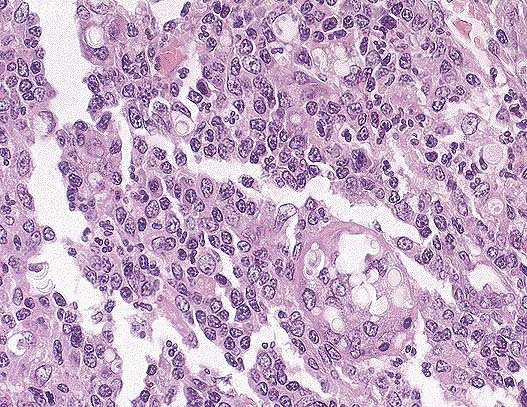

Higher magnification of the nematode eggs and larva, whch are characteristic for Aelurostrongylus abstrusus infection in the cat. Close inspection of one of the larve shown above reveals the presence of a caudal spine of the first stage larva's posterior end. A mild subacture and eosinophilic interstitial pneumonia is present in areas containing the nematodes. (HE, 400X, 90K)

Alveoli and alveolar ducts in a large area of lung parenchyma are distended with nematode larvae and embryonated eggs. Some alveoli are disrupted due to overexpansion with the larvae. The parasite larvae are compatible with Aelurostrongylus abstrusus.

Conference Note: Aelurostongylus abstrusus is a common metastongylid lungworm of cats. The genus is ovo-viviparous, the eggs hatching in the air passages. The L1 larvae are passed in the feces, enter a mollusc (snail or slug) intermediate host where they develop to L3 larvae in approximately 18 days. The mollusc may be eaten by birds, rodents, frogs, and lizards, which will carry the L3 larvae as paratenic hosts. The cat is infected by ingestion of the paratenic host or the mollusc. The L3 larvae migrate to the lung parenchyma and small bronchioles to complete the life cycle.

The pulmonary lesions are quite characteristic, usually being in the form of 1-10 mm diameter nodules, which represents nests of eggs and larvae. These nodules are yellowish and firm, scattered throughout the parenchyma but more common in the peripheral lung. A small amount of creamy exudate can be expressed from each nodule. Severe, confluent consolidation can produce clinical signs of chronic coughing and weight loss. Histologic lesions include dense collections of mononuclear cells, and occasional giant cells especially around degenerate larvae. There is often bronchiolar smooth muscle hyperplasia, catarrhal and eosinophilic bronchiolitis, hyperplasia of submucosal glands and smooth muscle hypertrophy and hyperplasia within pulmonary arterial walls. The granulomatous alveolitis and catarrhal bronchiolitis gradually regresses. However, the hypertrophy and hyperplasia of the smooth muscle in arteries, bronchioles and alveolar ducts persists.